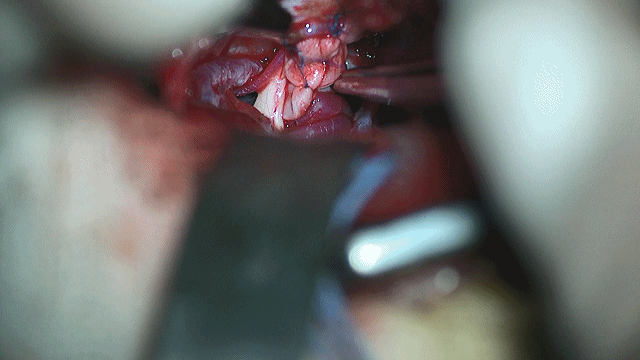

术中发现左侧椎动脉粗大,与左侧三叉神经紧贴,且有蛛网膜粘连带形成。只有一张垫片可用,此情况下选择用人工硬膜制作“脑膜托”悬吊左侧椎动脉,再置入垫片少许预防性垫隔。术后复查头颅CT未见异常,术后至今未再发生三叉神经痛。

术中椎动脉粗大,此时想到“黾”字,先做“脑膜探子”一枚,普林线连结“脑膜托”,将脑膜成功环绕椎动脉,并将其悬吊在岩面硬膜,缝合固定2针。术中效果满意,回顾以往阅读文献及结合北京天坛医院所见所闻,类似病例不胜枚举,觉探子和脑膜托类似“黾(mǐn)”字,故分享。